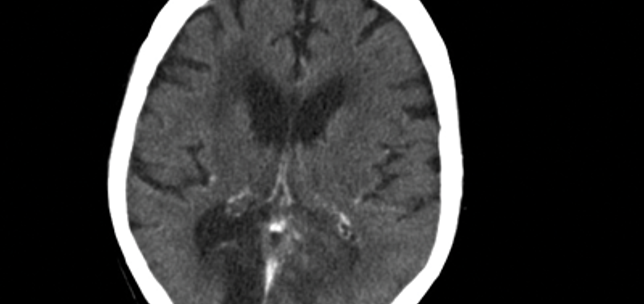

Cortical blindness

Shampa Gupta

JVK Sardar

1st August 2014

Education

Case Reports